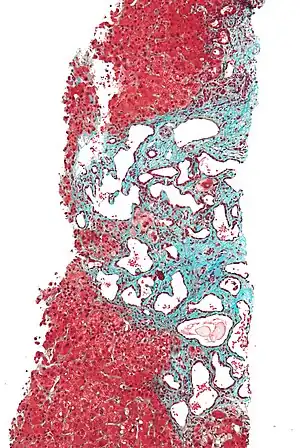

Low magnification micrograph of a bile duct hamartoma. Trichrome stain.